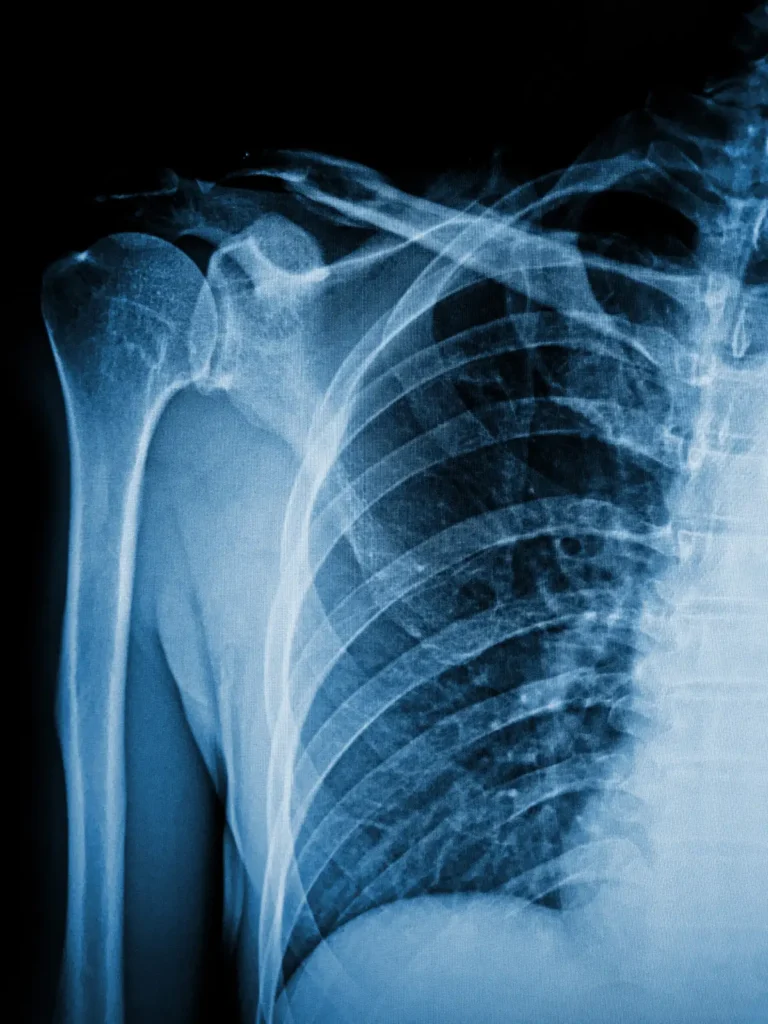

Shoulder Dislocated Shoulder August 29, 2024 Read More Shoulder Arthritis and Total Shoulder Replacement August 29, 2024 Read More Frozen Shoulder (Adhesive Capsulitis) August 24, 2024 Read More Shoulder Impingement Syndrome August 24, 2024 Read More Rotator Cuff Injuries (Tendinitis/Tendinopathy and Tears) August 24, 2024 Read More